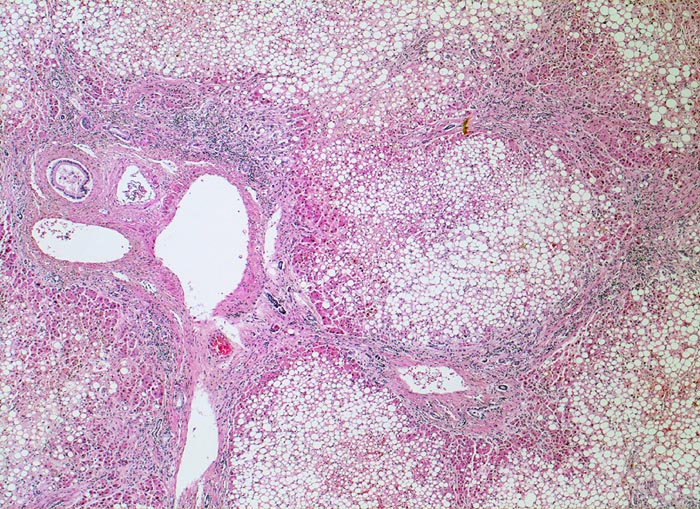

• Vollständiger feinknotiger zirrhotischer Umbau.

• Gemischtes portales, septales und intralobuläres Entzündungsinfiltrat.

• Floride sklerosierende alkoholische Steatohepatitis: Grobtropfige Verfettung von ca. 50% des Parenchyms.Neutrophile Granulozyten umgeben einzelne Hepatozyten (Satellitose). Wenig Apoptosekörperchen. Zahlreiche Mallory Körperchen und Megamitochondrien. Perivenuläre Maschendrahtfibrose.

• Hydropische Schwellung periportaler Hepatozyten.

• Canaliculäre Cholestase in einem Zirrhoseknoten.